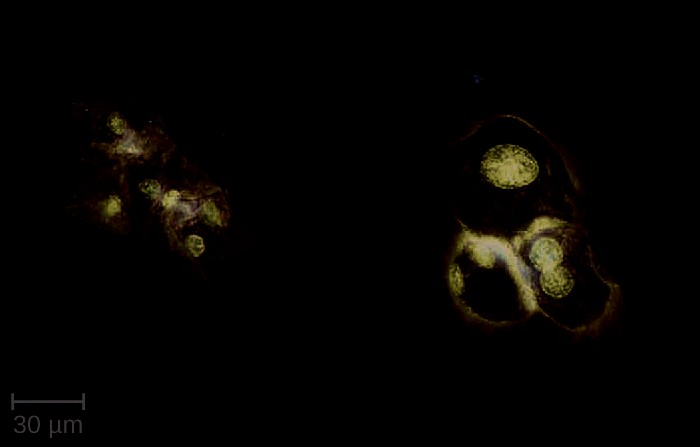

Figure 23.21 Candida blastospores (asexual spores that result from budding) and chlamydospores (resting spores produced through asexual reproduction) are visible in this micrograph. (credit: modification of work by Centers for Disease Control and Prevention)